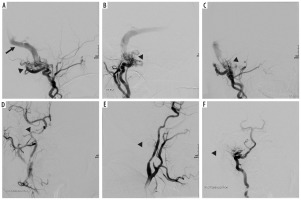

Figure 3

Digital subtraction angiography showing complex dural arteriovenous fistula, which was supplied by numerous feeders from right occipital, right sided ascending pharyngeal, posterior auricular and right vertebral artery. Venous return through occluded pouch of right sigmoid sinus, which then further flowed retrogradely into transverse and superior sagittal sinus and from there into superficial cortical veins and then into deep venous system, with final drainage into cavernous sinus, inferior petrosal sinus and ophthalmic vein (black arrowheads showing the fistula in images A-C, black arrow indicating venous return in image A). Subsequently, a microcatheter was placed in the right occipital artery and its embolization was performed using Onyx. Furthermore, using a separate microcatheter, cannulation of right ascending pharyngeal and posterior auricular arteries was performed one by one, followed by their embolization using Onyx procedure; angiogram shows 90% embolization of the feeders achieved. Minor filling was noted from vertebral feeder. Sluggish flow of the contrast from vertebral artery feeders was noted. Venous phase showed contrast stasis in transverse and superior sagittal sinuses (post-embolization sites indicated by arrowheads in images D-F)